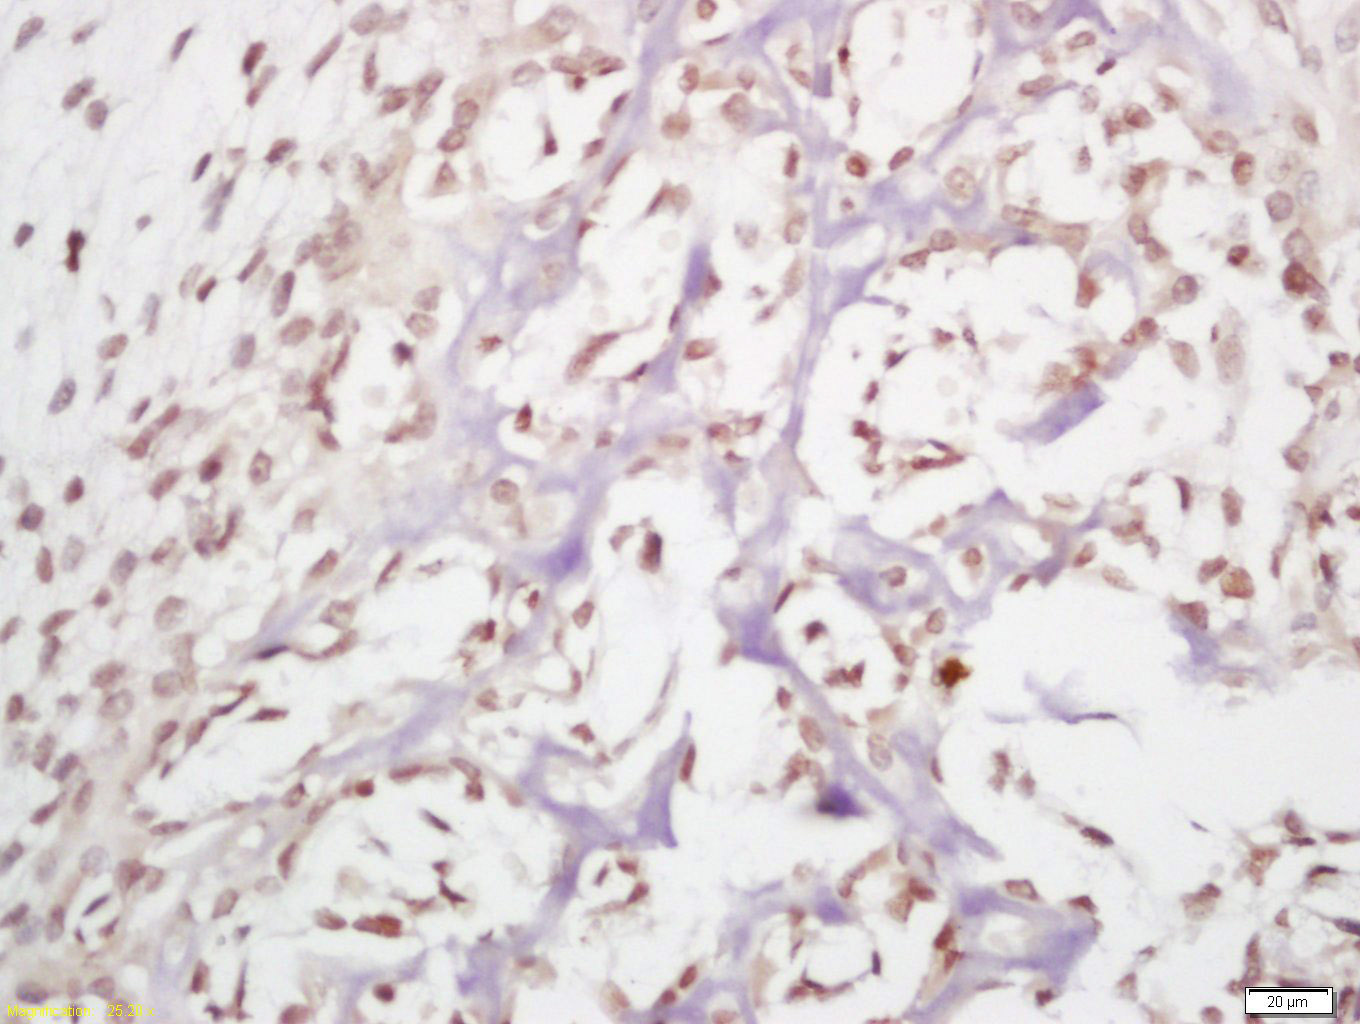

Antigen retrieval: citrate buffer ( 0.01M, pH 6.0 ), Boiling bathing for 15min; Block endogenous peroxidase by 3% Hydrogen peroxide for 30min; Blocking buffer (normal goat serum,C-0005) at 37℃ for 20 min;

Incubation: Anti-HDAC11 Polyclonal Antibody, Unconjugated(bs-2894R) 1:200, overnight at 4°C, followed by conjugation to the secondary antibody(SP-0023) and DAB(C-0010) staining